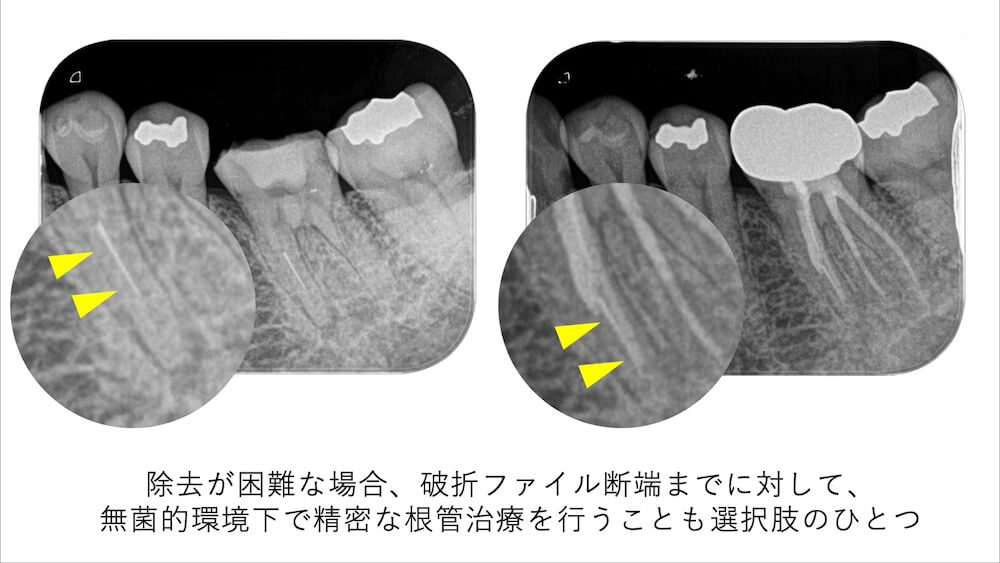

そのような場合には無理に歯質を切削して除去を試みるのではなく、”ファイル断端までを無菌的環境(ラバーダム環境)でしっかりと清掃することが有効な選択肢である”といわれています。